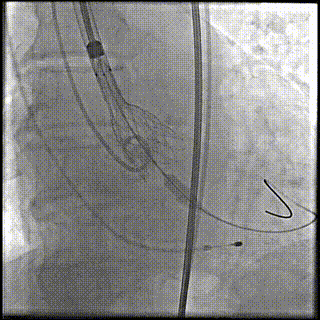

第二次释放到工作位,位置理想

瓣膜完全释放

瓣膜完全释放后造影

外周造影

植入后评估:

植入后血流动力学改善明显